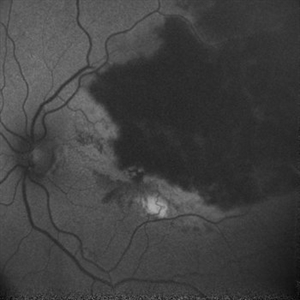

RPE rip in a case of Idiopathic polypoidal choroidopathy RPE rip in a case of Idiopathic polypoidal choroidopathyOct 23 2022 by Anjana Mirajkar, MS Ophthalmology Montage of Fluorescein angiography in a of 61 year old male with RPE rip in a case of Idiopathic Polypoidal Choroidopathy. Photographer: Dr. Anjana Mirajkar -Retina Foundation, Ahmedabad Condition/keywords: Idiopathic polypoidal choroidopathy, RPE rip